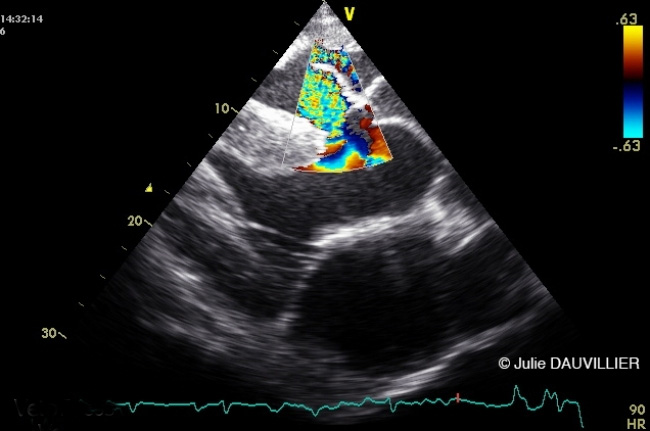

CARDIOLOGIE ÉQUINE

Les cours minute en CARDIOLOGIE ÉQUINE sont présentés par Julie DAUVILLIER, Vétérinaire équin spécialiste en médecine interne.

Dans ce programme UVC5 de 29 cours minutes d’introduction à la CARDIOLOGIE ÉQUINE, nous verrons comment optimiser l'examen clinique et l'auscultation cardiaque pour en tirer un maximum d’informations. Nous apprendrons notamment à caractériser les souffles et à les identifier.